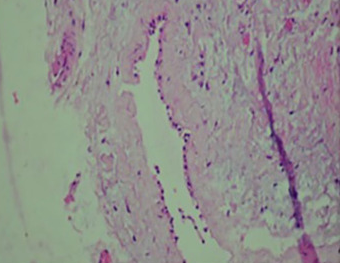

Histopathological examination of parathyroid adenocarcinoma (Courtesy Dr. V. Penopoulos)